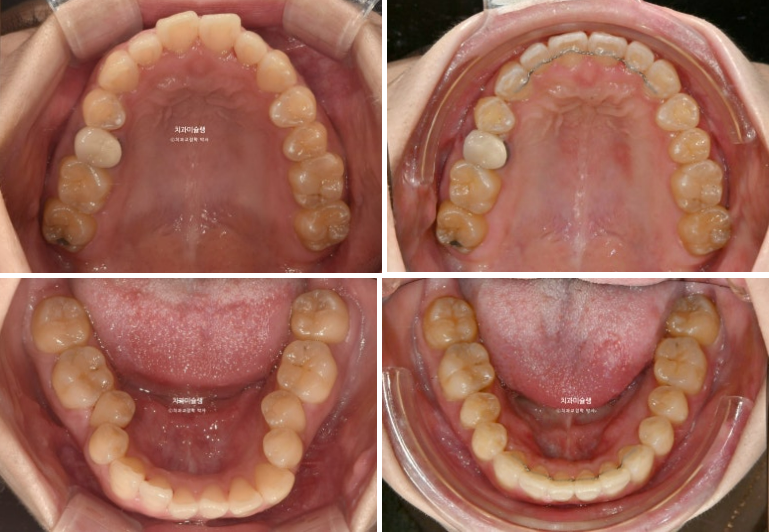

이제 전후비교 보겠습니다.

총 치료기간은 1년 5개월, 재제작은 1회 했습니다.

유지장치까지 들어간 모습입니다.

24.06~25.11

아래 앞니 잇몸은 처음에 비해 소량 차올랐습니다. 앞니 뿌리가 치조골 안으로 안정적으로 들어가도록 치료계획을 세웠기 때문이고 이처럼 30대 성인이라도 가끔 회복되는 경우가 있습니다.